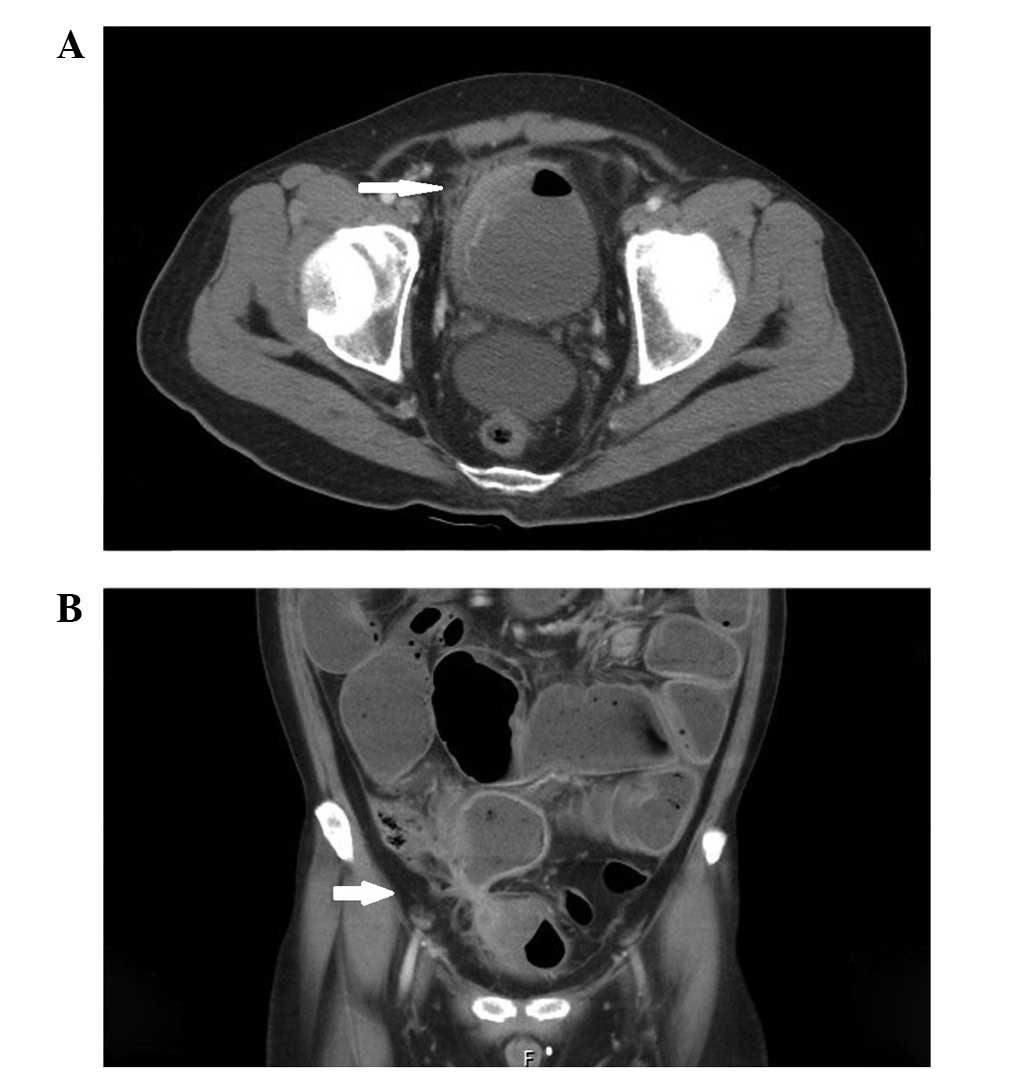

Fistulas In Malignant Gynecologic Disease: Etiology, Imaging ...

May be a complication of surgery or radiation therapy. Identification of the cause, Fistulas in Malignant Gynecologic Disease: Etiology, Imaging, and Management1 ONlINE-ONly CME vesicovaginal fistula (arrow) and a bladder catheter that has prolapsed into the vagina (arrowhead). (b) ... Doc Viewer